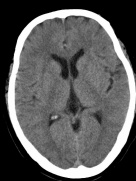

CT检查又贵还有辐射,重复检查是不是就是浪费钱还过度检查了?其实一些情况下,重复检查很有必要。比如对于缺血性脑梗死的患者,早期在颅脑CT上可能没有异常,大约24小时后才能见到因缺血而造成的低密度脑梗死灶。碰到这种情况,要结合病史、病人现况,在24小时后或者更长时间以后给予CT复查,确认诊断。比如,下图中,左图为患者左侧肢体乏力4小时后的颅脑CT图像,右图为患者两天后的颅脑CT图像。发病4小时后的颅脑CT图未见明显异常,而2天后可见大面积的低密度脑梗死灶。

发病4小时后的颅脑CT图